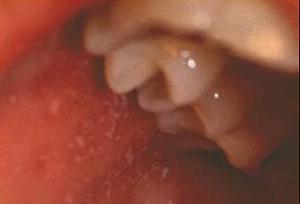

口腔麻疹粘膜斑(疾病图谱)